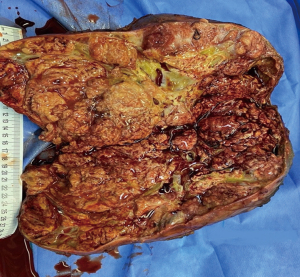

The specimen sent to the histopathology department was preserved in formalin and showed a huge adrenal mass, spleen, and part of the pancreas. The tumor measured 31 cm × 21 cm × 17 cm (Figure 4) and weighed 4.7 kg (Figure 5).

The slides showed ACC with vascular invasion and violation of the capsule. The pancreatic tissue revealed focal sclerosing pancreatitis and no sign of invasion of the pancreas or spleen (Figure 6). Based on these findings, the tumor was classified as ENSAT stage III per the ENSAT staging criteria.